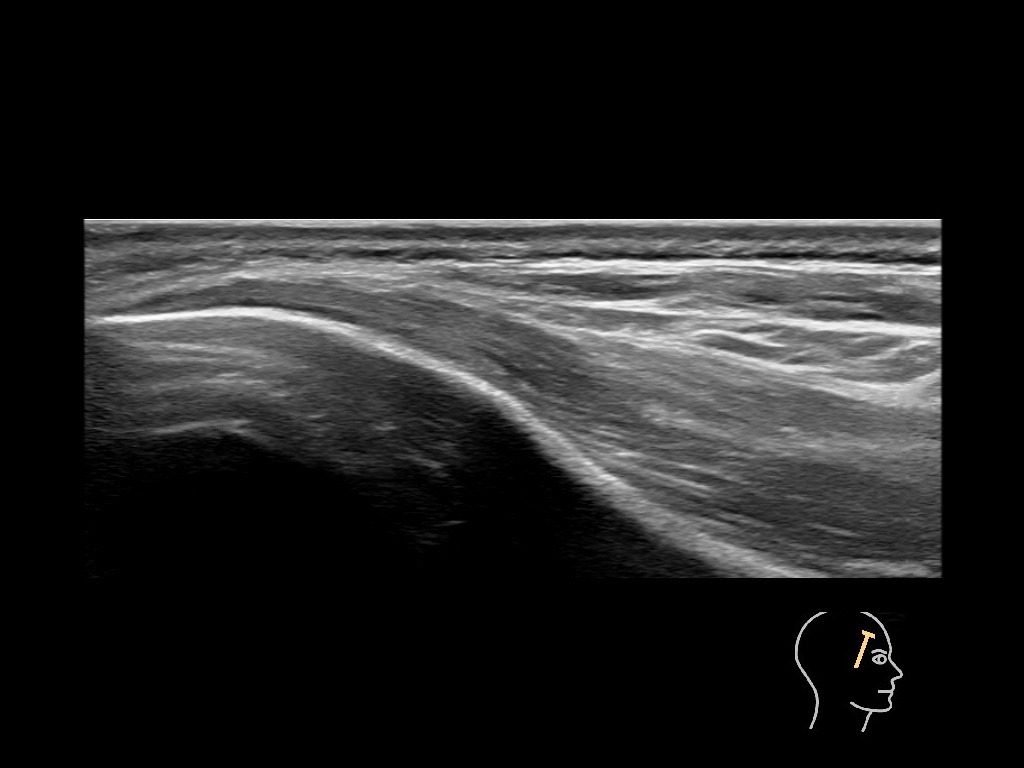

Draw in the second image below where the fillers are located. To check if your answer is correct, swipe the first image to the right.